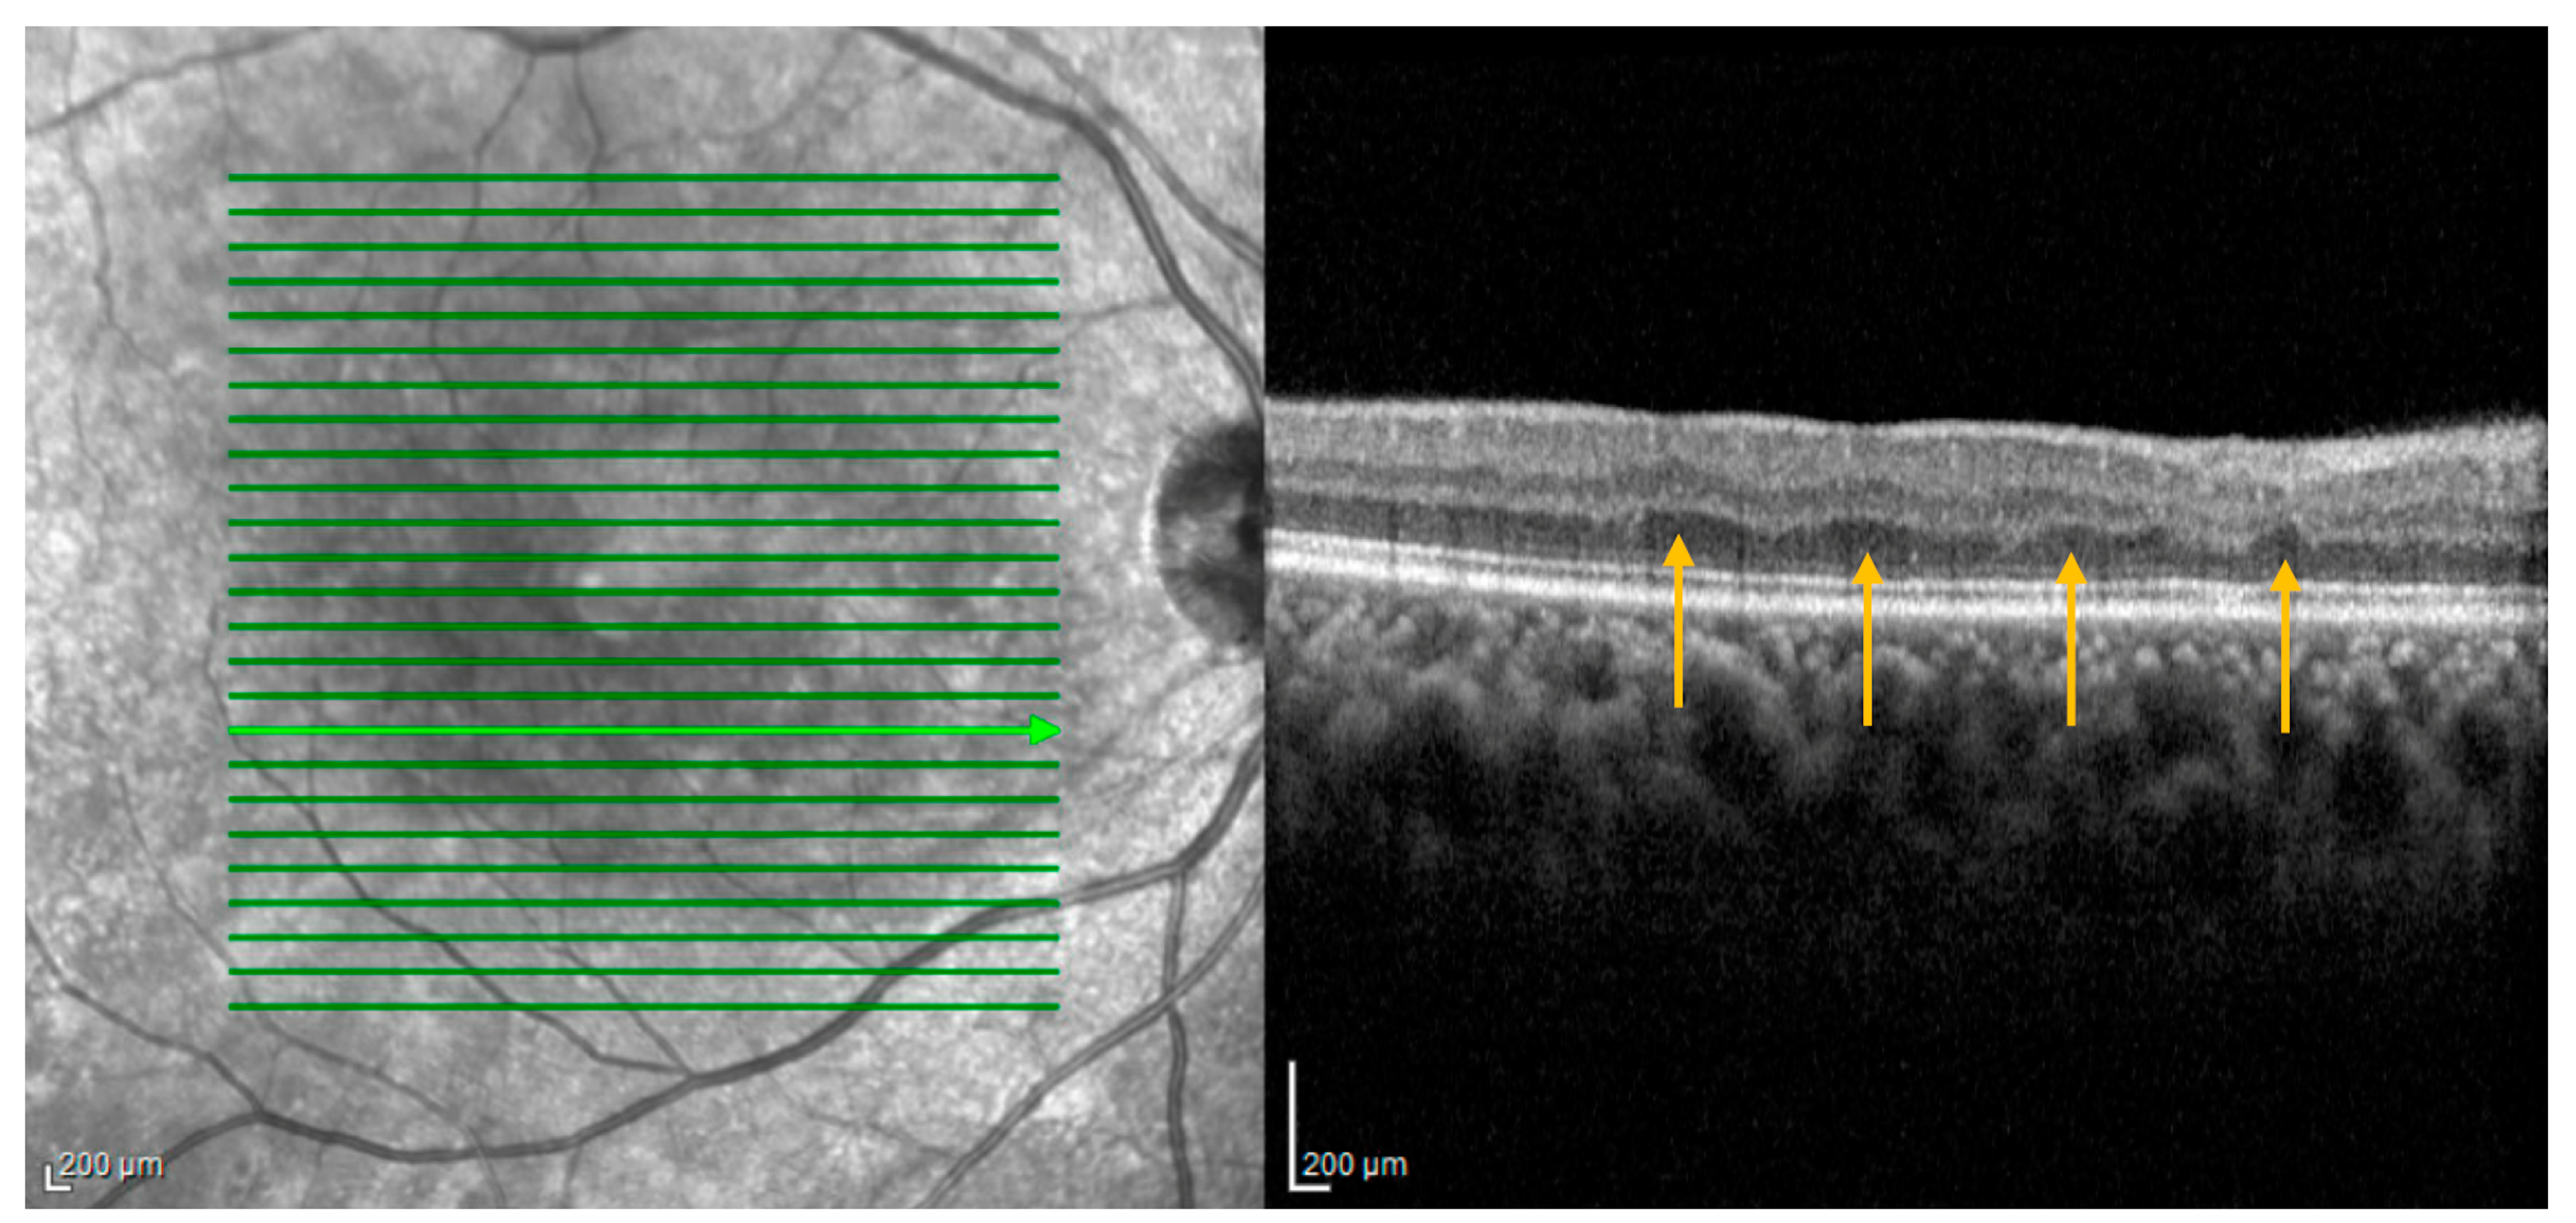

3.1.4. Age-Related Macular Degeneration: Subretinal Drusenoid Deposits

- Agrón, E.; Agrón, E.; Domalpally, A.; Domalpally, A.; Cukras, C.A.; Cukras, C.A.; Clemons, T.E.; Clemons, T.E.; Chen, Q.; Chen, Q.; et al. Reticular Pseudodrusen: The Third Macular Risk Feature for Progression to Late Age-Related Macular Degeneration: Age-Related Eye Disease Study 2 Report 30. Ophthalmology 2022, 129, 1107–1119. [Google Scholar] [CrossRef] [PubMed]

- Veerappan, M.; El-Hage-Sleiman, A.-K.M.; Tai, V.; Chiu, S.J.; Winter, K.P.; Stinnett, S.S.; Hwang, T.S.; Hubbard, G.B.; Michelson, M.; Gunther, R.; et al. Optical Coherence Tomography Reflective Drusen Substructures Predict Progression to Geographic Atrophy in Age-related Macular Degeneration. Ophthalmology 2016, 123, 2554–2570. [Google Scholar] [CrossRef] [PubMed]

- Thomson, R.J.B.; Chazaro, J.B.; Otero-Marquez, O.; Ledesma-Gil, G.; Tong, Y.; Coughlin, A.C.B.; Teibel, Z.R.; Alauddin, S.; Tai, K.B.; Lloyd, H.B.; et al. Subretinal drusenoid deposits and soft drusen: Are they markers for distinct retinal diseases. Retina 2022, 42, 1311–1318. [Google Scholar] [CrossRef]

- Cymerman, R.M.; Skolnick, A.H.; Cole, W.J.; Nabati, C.; Curcio, C.A.; Smith, R.T. Coronary Artery Disease and Reticular Macular Disease, a Subphenotype of Early Age-Related Macular Degeneration. Curr. Eye Res. 2016, 41, 1482–1488. [Google Scholar] [CrossRef]

- Liang, C.; Wang, N. Subretinal Drusenoid Deposits and Lower Serum High-Density Lipoprotein Cholesterol Levels Possess Latent Relation to Cardiovascular Disease and Can Be a Feasible Predictor. Comput. Math. Methods Med. 2022, 2022, 3135100. [Google Scholar] [CrossRef]